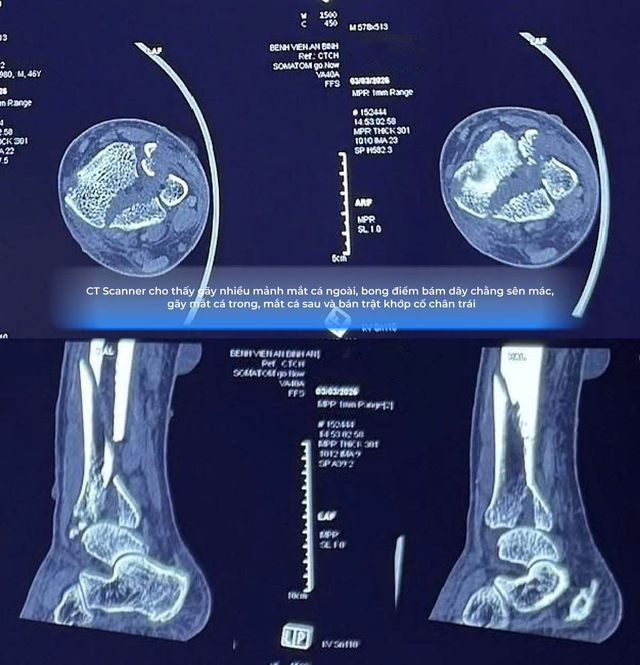

Sau khi tiến hành thăm khám lâm sàng kết hợp các phương tiện chẩn đoán hình ảnh như X-quang và CT scan, các bác sĩ Khoa Chấn thương chỉnh hình xác định bệnh nhân mắc nhiều tổn thương nghiêm trọng cùng lúc.

Trước hết, bệnh nhân bị gãy phức tạp ba mắt cá chân, một dạng chấn thương nặng làm mất hoàn toàn tính vững của khớp cổ chân. Đây là tổn thương thường gặp trong các chấn thương xoay mạnh của cổ chân và nếu không điều trị đúng cách có thể dẫn đến biến dạng khớp vĩnh viễn.

Ngoài ra, bệnh nhân còn gãy 1/3 dưới xương chày, là phần xương dài chịu lực chính của cơ thể khi đứng và di chuyển. Sự kết hợp giữa hai loại gãy xương này khiến cấu trúc cổ chân gần như mất hoàn toàn sự ổn định.

Chưa dừng lại ở đó, các bác sĩ còn phát hiện bán trật khớp cổ chân, nghĩa là các diện khớp đã bị xê dịch khỏi vị trí giải phẫu bình thường.